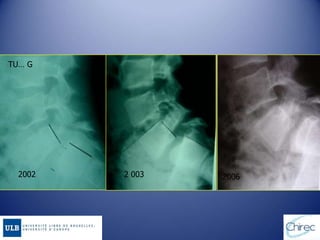

TU… G

2002 2 003 2006

HISTOIRE NATURELLE Rupture isthmiquedu grand enfant parfois de l’adolescent sous l’effet de facteurs favorisants (microtraumatismes +++) SPONDYLOLYSE UNI OU BILATERALE Consolidation spontanée ou après traitement Pérennisation de la lyse Formes peu ou pas déplacées « Fracture de fatigue » J.L Jouve